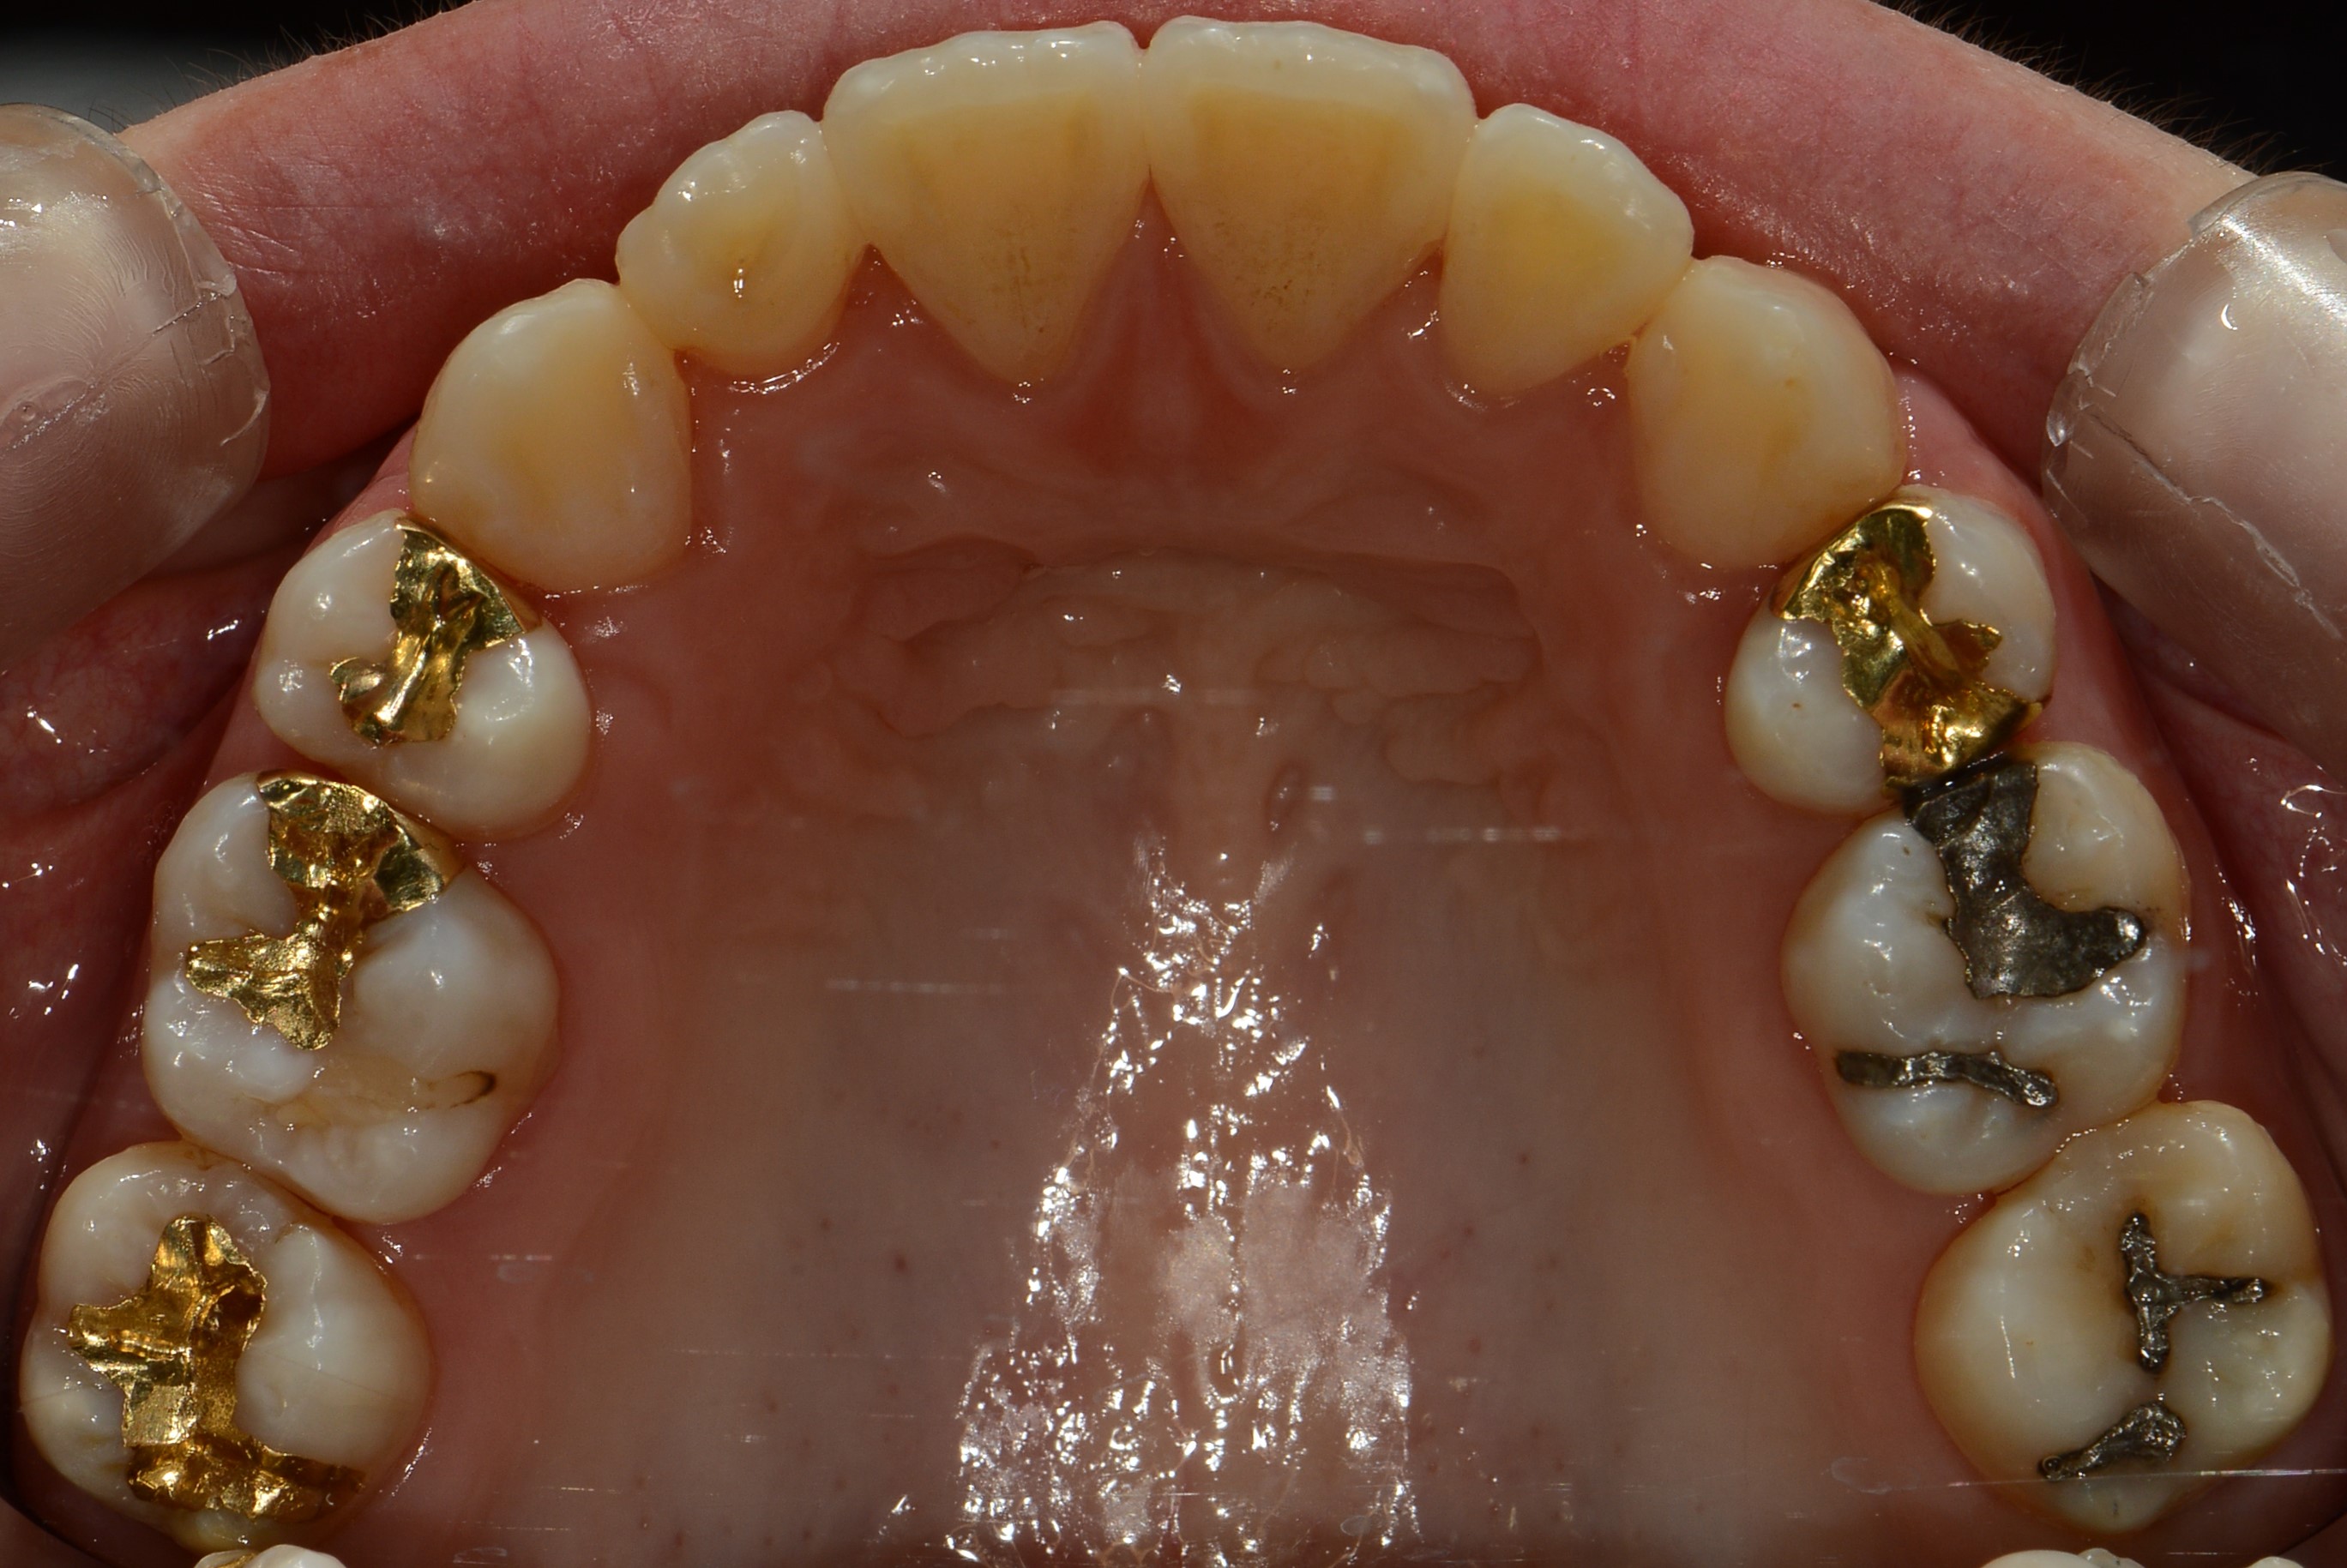

치료 전 사진입니다.